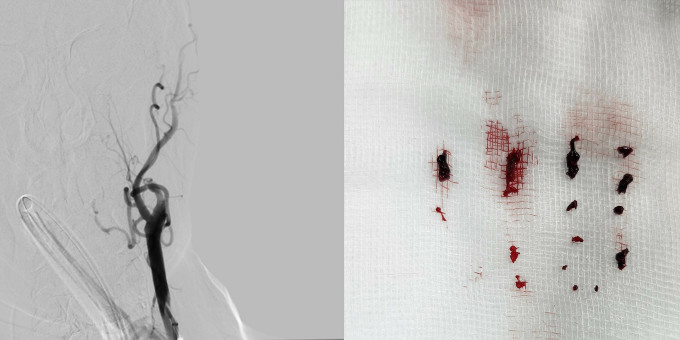

TPHCM: Người đàn ông 64 tuổi đột quỵ do có hơn 10 cục máu đông trong não

Ông T, 64 tuổi, ngụ TPHCM bị đột quỵ do tắc nhiều động mạch não cùng lúc, bác sĩ can thiệp lấy hơn 10 cục máu đông trong não.